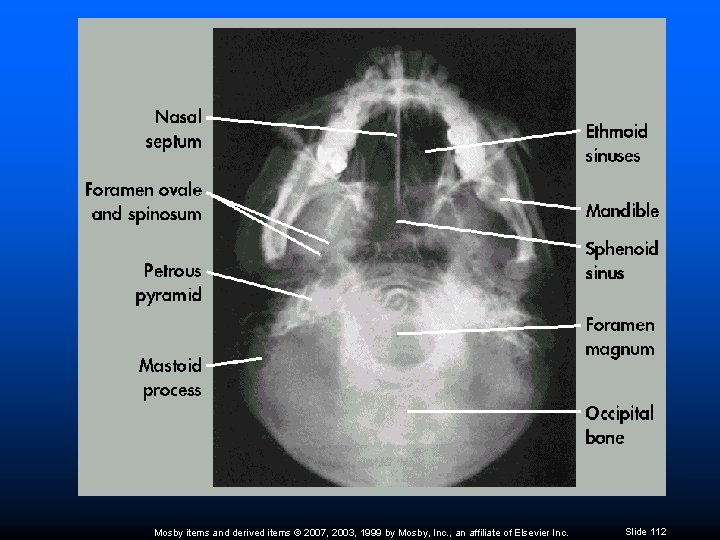

SMV Projection (Schüller) No rotation or tilt Equal distance from lateral border of skull to mandibular condyles Ø Symmetric petrous pyramids Ø Penetration sufficient to demonstrate structures of cranial base Mosby items and derived items © 2007, 2003, 1999 by Mosby, Inc. , an affiliate of Elsevier Inc. Slide 109

SMV Projection (Schüller) Superimposition of mental protuberance over anterior frontal bone, indicating full neck extension Mandibular condyles anterior to petrous pyramids Mosby items and derived items © 2007, 2003, 1999 by Mosby, Inc. , an affiliate of Elsevier Inc. Slide 110

SMV Projection (Schüller) Superimposition of mental protuberance over frontal bone – indicates full neck extension Condyles of mandible anterior to petrous pyramids Mosby items and derived items © 2007, 2003, 1999 by Mosby, Inc. , an affiliate of Elsevier Inc. Slide 111

Mosby items and derived items © 2007, 2003, 1999 by Mosby, Inc. , an affiliate of Elsevier Inc. Slide 112